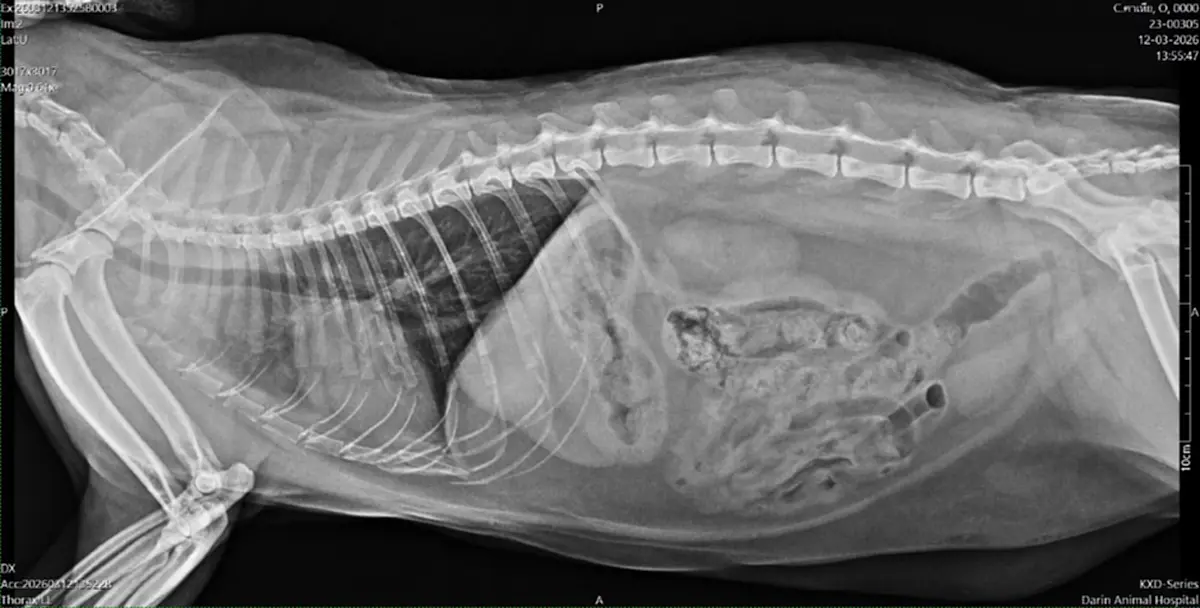

จนวันนึงถึงคราวตรวจสุขภาพประจำปี เอ็กซ์เรย์แล้วพบปอดอักเสบแบบเข้าขั้นเยอะ ถึงเยอะมากเลยล่ะ

จากภาพจะมีบริเวณที่เป็นฝ้าขาว ด้านซ้ายของรูป ใต้กระดูก คุณหมอจะอ่านภาพและชี้จุดให้